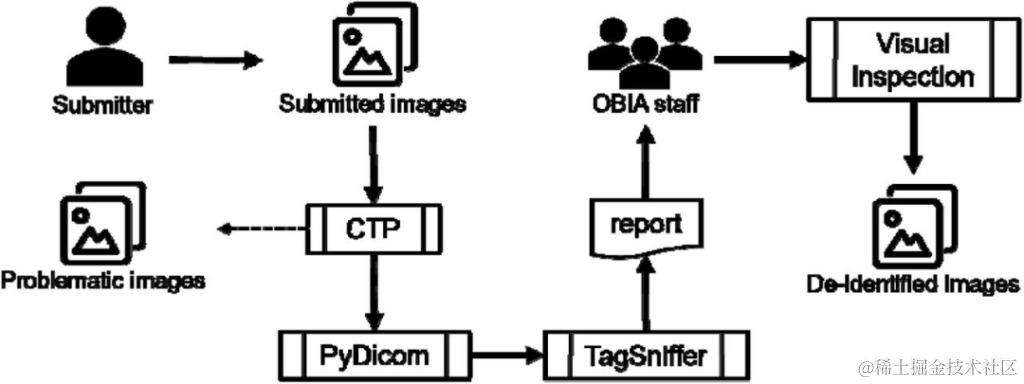

数据库内容及使用——去标识化和质量控制

生物医疗图像可能包含受保护的健康信息 (PHI,Protected Health Information),需要经过适当处理以尽量降低侵犯个人隐私的风险。为了在删除 PHI 的同时尽可能多地保留有价值的科学信息,OBIA 提供了一个符合 DICOM 标准的去标识化和质量控制机制 (图 4)。

图 4:OBIA 去标识化和质量控制机制

OBIA 利用北美放射学会 (RSNA) 的 MIRC 临床试验处理器 (CTP) 进行大部分去标识化工作:

• 对于标准标记 (standared tags), 研究人员构建了一个 CTP ,并开发了一个通用的基础去标识化脚本,用于删除或隐去某些包含或可能包含 PHI 的标准标记;

• 对于私有标记 (private tags), 使用 PyDicom 进行处理,保留其纯数字属性。

去标识过程结束后,OBIA 开始运行质量控制程序:

• 有问题的图像: 隔离图像,提交者可以提供相关信息对图像进行修复或完全抛弃(该类图像是指带有空白标题或缺少患者 ID、损坏、混合了其他患者图像等类型的图像);

• 重复的图像: 只保留一个。

随后 OBIA 使用 TagSniffer 为所有图像生成一个报告,报告中所有 DICOM 元素都经过仔细审查,以确保它们不包含 PHI,并且某些值(例如患者 ID、研究日期)按照预期进行修改。

此外,OBIA 工作人员还会对图像像素执行目视检查, 以确保像素值中没有包含 PHI,并且图像是可见和未损坏的。